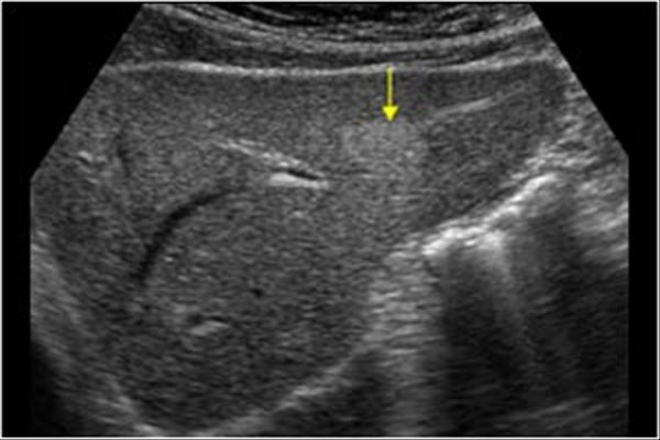

Exploración ultrasonográfica renal

La ultrasonografía del sistema urinario es una herramienta diagnostica de apoyo en el ejercicio de la profesión médica, pues permite un diagnóstico y tratamiento oportuno de las patología renales a través de la evaluación de las estructuras anatómicas del paciente mediante sonido. Además es un técnica que se puede usar